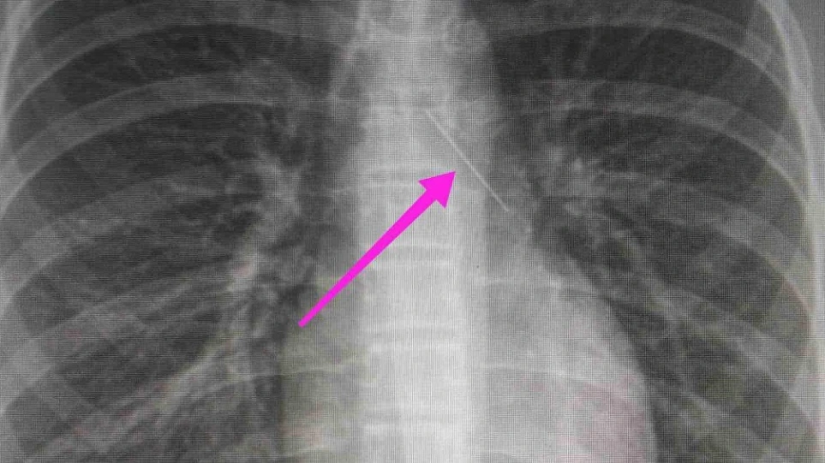

Από την απεικονιστική διερεύνηση που πραγματοποιήθηκε με ακτινογραφία θώρακος αρχικά και ακολούθως με αξονική τομογραφία θώρακος, διαπιστώθηκε η ύπαρξη αιχμηρού μεταλλικού ξένου σώματος στην αναπνευστική οδό (δεξιός κύριος βρόγχος) και όχι στην πεπτική οδό, αναφέρει η ανακοίνωση του νοσοκομείου, στα μέσα κοινωνικής δικτύωσης.

“Χθες 30/1/2022 στις 16:00 στο Τ.Ε.Π. του ΓΝΘ Ιπποκράτειο, προσήλθε ανήλικη συνοδευόμενη από τους γονείς της, μετά από αναφερόμενη κατάποση ξένου σώματος (καρφίτσα). Από την απεικονιστική διερεύνηση που πραγματοποιήθηκε με ακτινογραφία θώρακος αρχικά και ακολούθως με αξονική τομογραφία θώρακος, διαπιστώθηκε η ύπαρξη αιχμηρού μεταλλικού ξένου σώματος στην αναπνευστική οδό (αριστερός κύριος βρόγχος) και όχι στην πεπτική οδό.